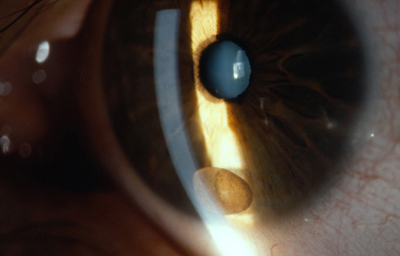

b - Persistencia de vasos cápsulo-pupilares que partiendo del circulo menor, se dirigen hacia detrás del cristalino como en los casos de coloboma, pero pueden existir sin interferir en el crecimiento del Iris

c - Vasos persistentes unidos al cristalino en uno de sus extremos; parten del circulo menor y el otro extremo en contacto con el cristalino, produce una opacidad capsular anterior a veces de forma piramidal como si hubiera existido tracción sobre la cápsula.

Archivo fotográfico Dr. Carmen Barraquer